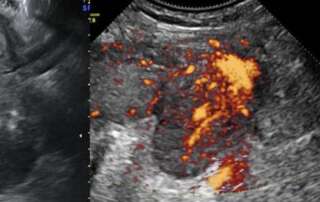

Left ovarian vein thrombophlebitis in the postpartum period